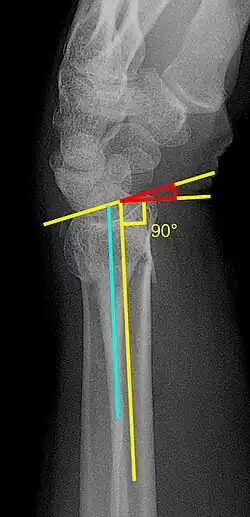

En outre, il se distingue par le développement de nouvelles procédures diagnostiques et thérapeutiques, telles que la prothèse cardan[4] ou la méthode de traitement de fractures de poignet[5].